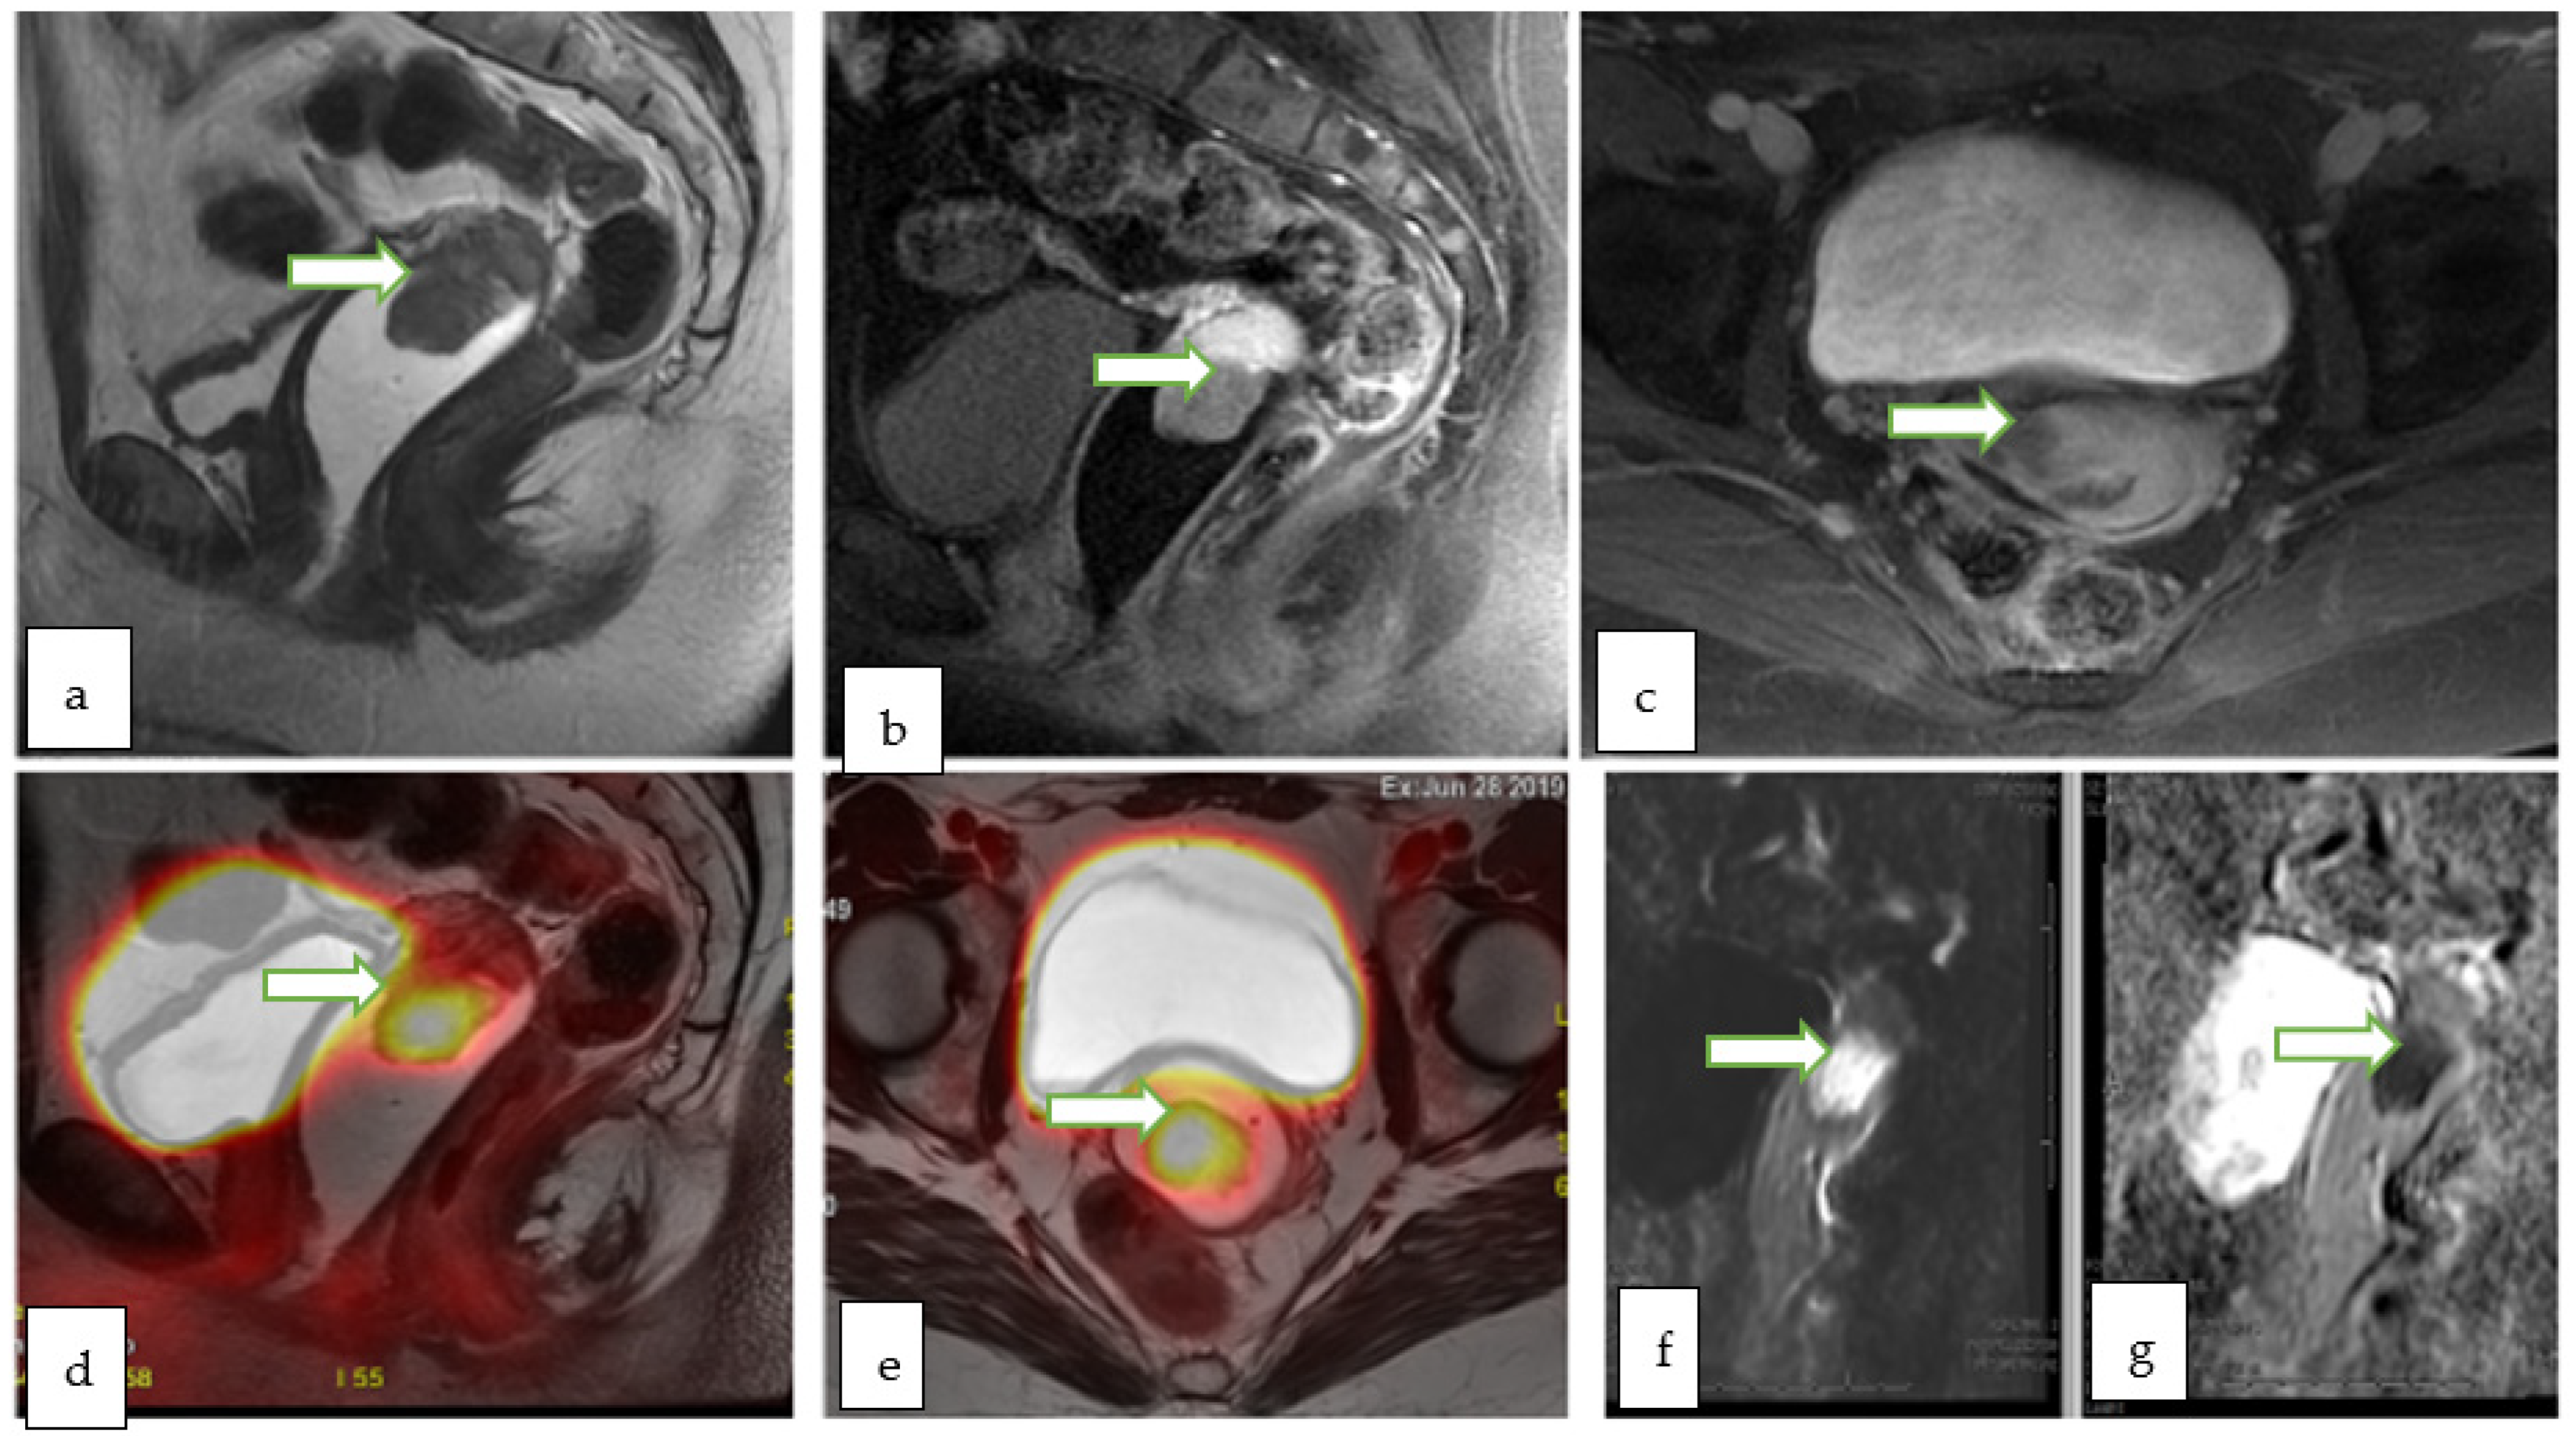

4.6. PET-MRI

- Ohliger, M.A.; Hope, T.A.; Chapman, J.S.; Chen, L.M.; Behr, S.C.; Poder, L. PET/MR Imaging in Gynecologic Oncology. Magn. Reson. Imaging Clin. N. Am. 2017, 25, 667–684. [Google Scholar] [CrossRef]

- Nguyen, N.C.; Beriwal, S.; Moon, C.-H.; D’Ardenne, N.; Mountz, J.M.; Furlan, A.; Muthukrishnan, A.; Rangaswamy, B. Diagnostic Value of FDG PET/MRI in Females With Pelvic Malignancy-A Systematic Review of the Literature. Front. Oncol. 2020, 10, 519440. [Google Scholar] [CrossRef]

- Virarkar, M.; Viswanathan, C.; Iyer, R.; de Castro Faria, S.; Morani, A.; Carter, B.; Ganeshan, D.; Elsherif, S.; Bhosale, P.R. The Role of Positron Emission Tomography/Magnetic Resonance Imaging in Gynecological Malignancies. J. Comput. Assist. Tomogr. 2019, 43, 825–834. [Google Scholar] [CrossRef]